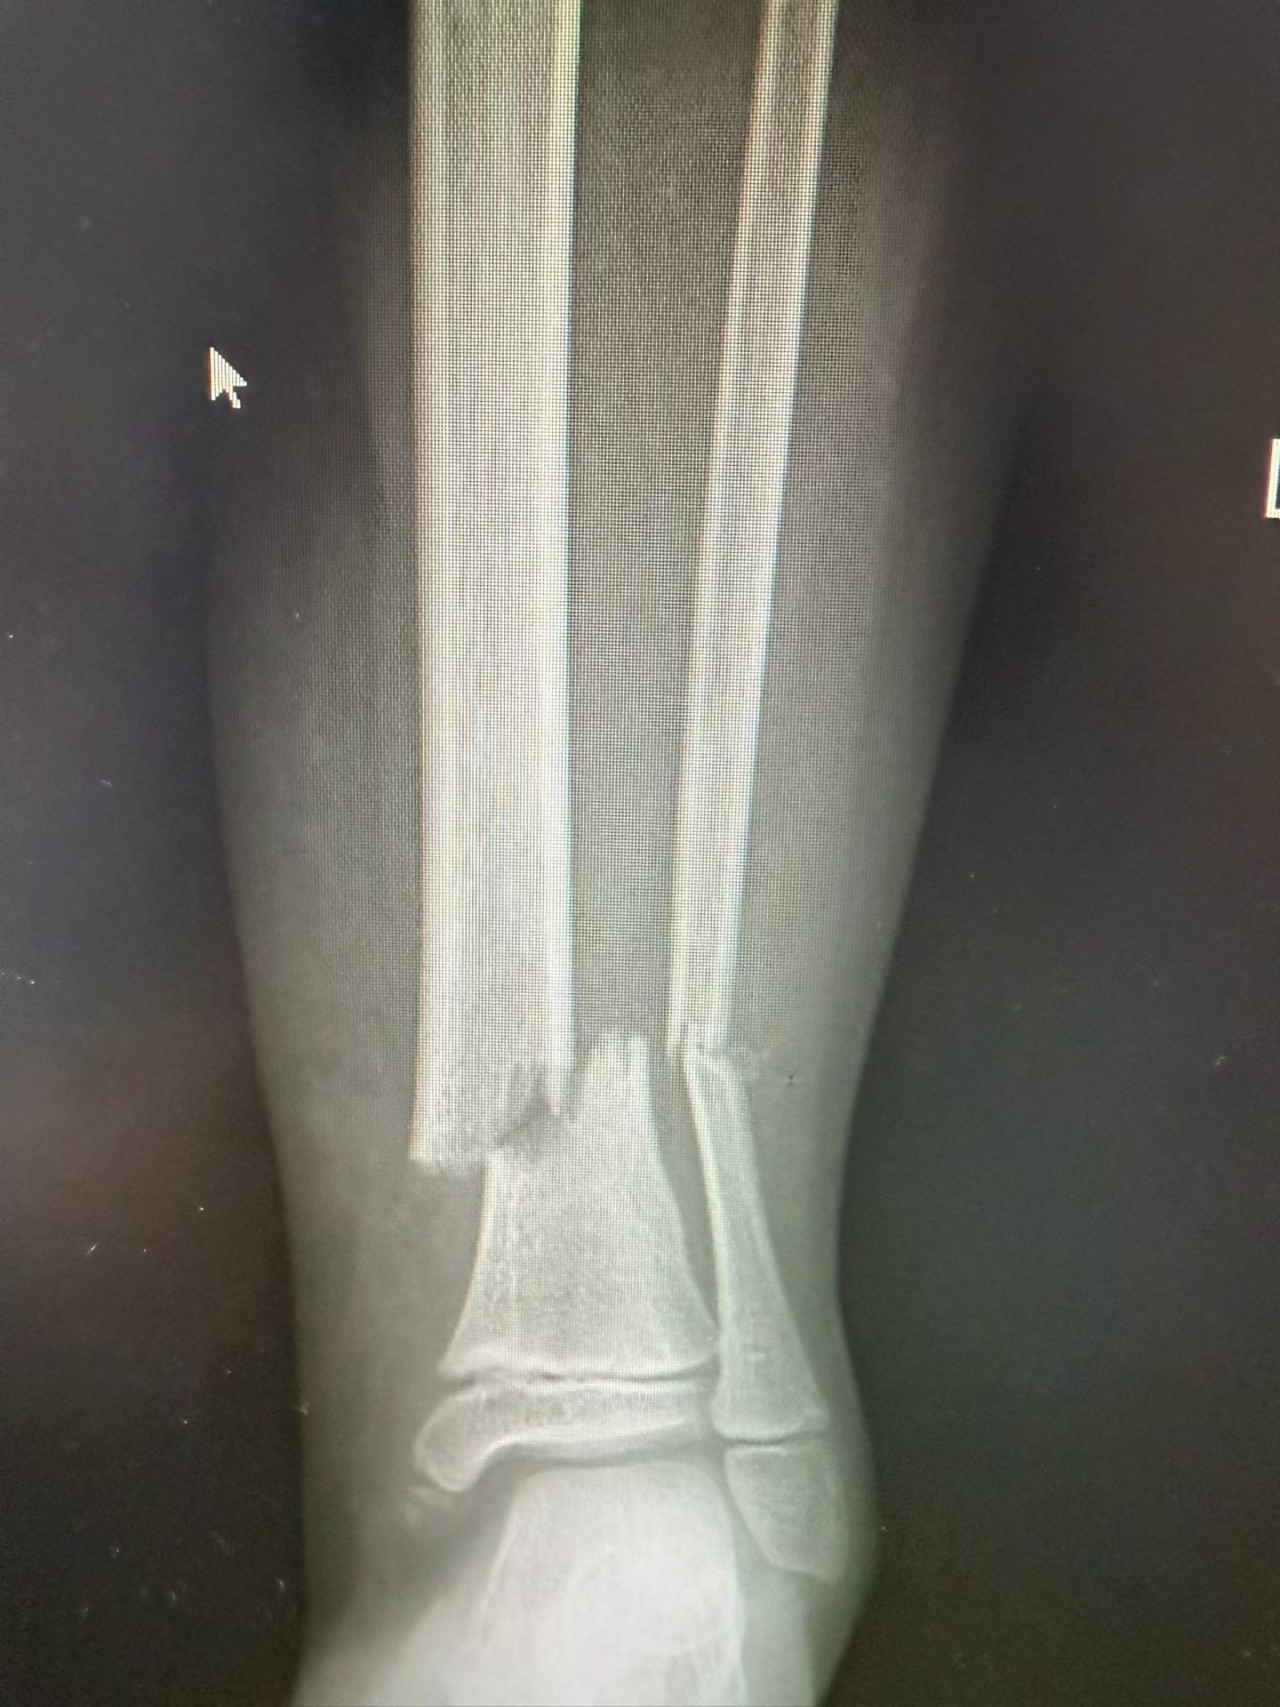

一张X光片的距离:从移位到精准复位

很多家长看到术前的X光片会吓一跳:孩子的骨头断端错位明显,甚至可能累及到负责骨骼生长的“骨骺”(生长板)。传统观念里,这可能需要大切口手术才能“看清”并“摆正”。

术前:影像清晰显示骨折位置,医生团队制定精准闭合复位方案。

术后:X光片显示骨折对位对线完美,而孩子的皮肤上只留下几个微小的针孔,几乎看不见疤痕。